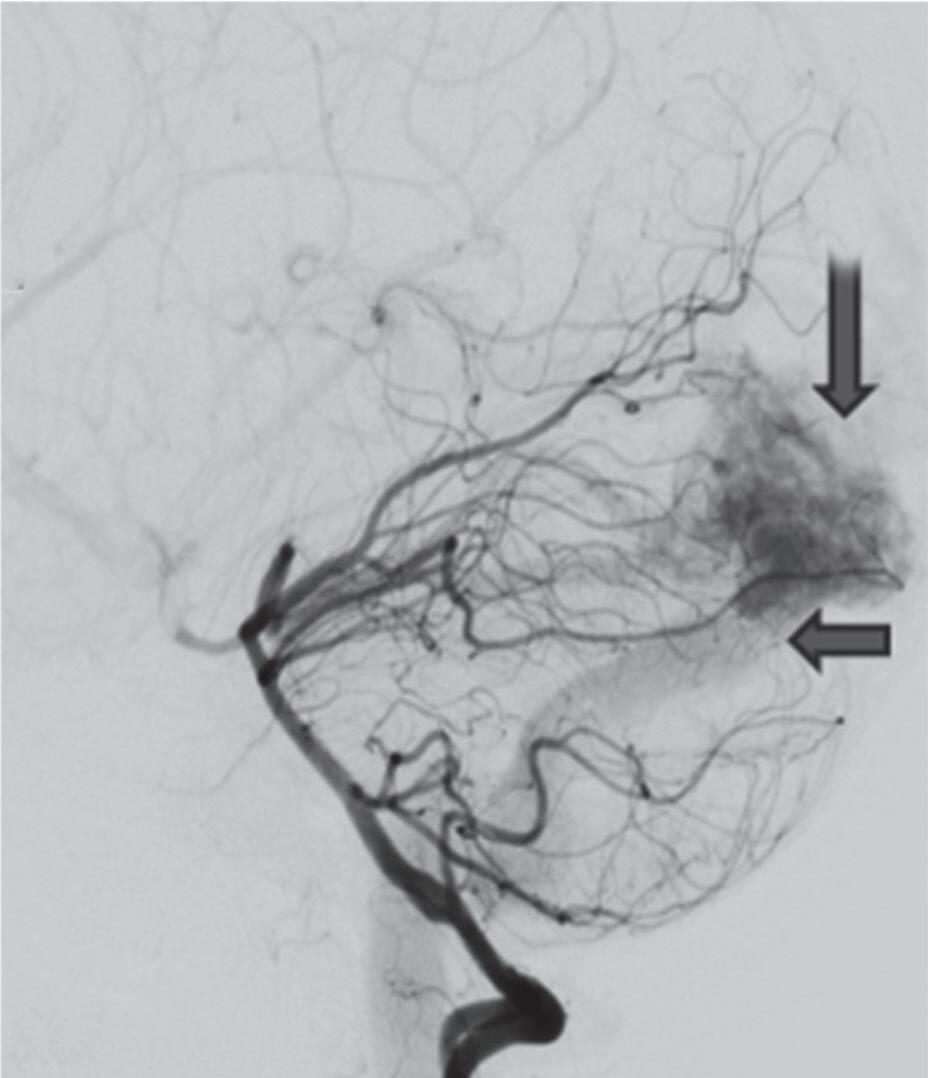

Fig. 1-8. (a-c) RNM T1 com contraste, cortes sagital (a), coronal (b) e axial (c) demonstrando MAV não rota com nidus localizado no lobo occipital à esquerda (setas longas). (d) Arteriografia digital cerebral com injeção de contraste via carótida direita (AP) mostrando a contribuição da carótida direita na irrigação da MAV contralateral. (e,f) Com injeção de contraste via carótida esquerda, em Perfil e AP respectivamente, observa-se nidus compacto nutrido por ramos da artéria cerebral média à esquerda e a veia de drenagem precoce se dirigindo para o seio sagital superior. Projeções em AP (g) e em perfil (h) demonstrando a contribuição do sistema vertebrobasilar por meio de ramos distais da artéria cerebral posterior à esquerda e drenagem para os seios sagital superior e sigmoide à esquerda (setas curtas).